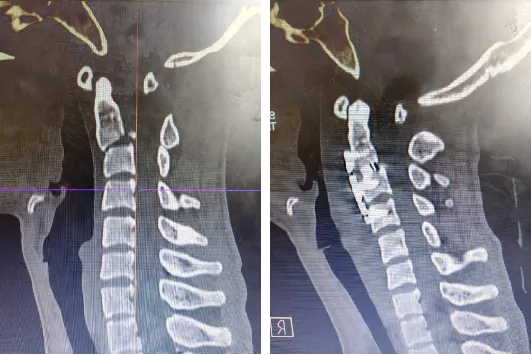

术前(左)与术后(右)影像学资料

为了拯救小夏,团队制定了详细周密的方案,由阿不都乃比·艾力主任医师主刀,先通过颅骨牵引+Mayfield头架将骨折精准复位,再在颈部右侧做4厘米美容切口(颈横纹处,愈合后几乎无痕),从气管、食管与大血管之间的“生命缝隙”深入6~8厘米,最终显露只有硬币大小的术野。最关键的置钉环节,医生将4枚螺钉精准打入C2-C4椎体,误差控制在0.5毫米以内,并植入零切迹钛合金固定装置。整个手术出血仅60毫升。